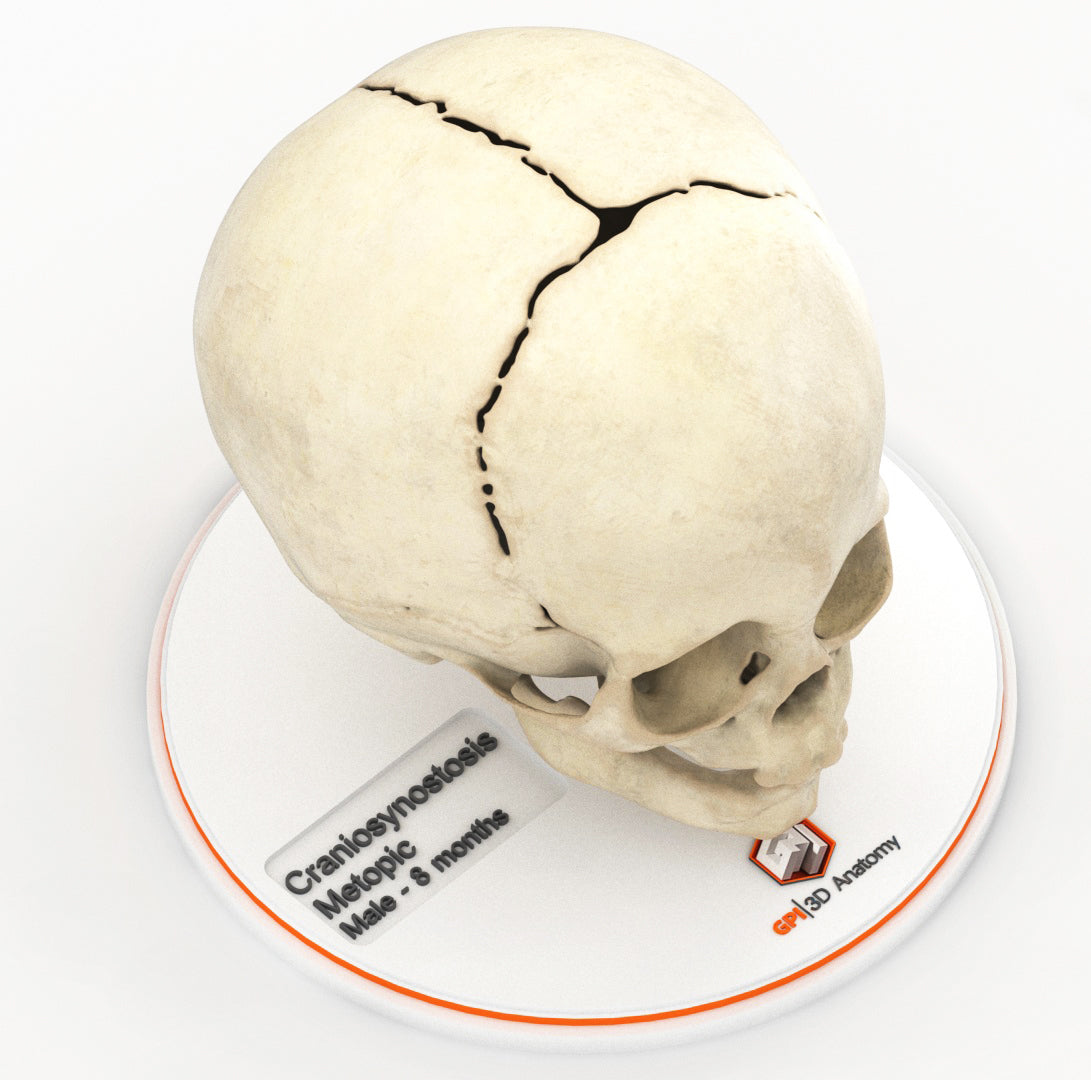

Infant Skull With Craniosynostosis of the Metopic Suture - Male, 8 Months

Infant Skull With Craniosynostosis of the Metopic Suture - Male, 8 Months

Craniosynostosis, a condition in which one or more cranial sutures in the infant skull prematurely mineralize and fuse before completion of brain development, with affected sutures:

Metopic synostosis (trigonocephaly) – The metopic suture separates two frontal bones in the cranial vault and runs from the nose to the sagittal suture at the top of the head. Premature fusion causes a triangular head shape, narrow in the front and broad in the back, with a metopic ridge at the midline of the forehead.

Designed using MRI and CT imaging scans and the latest 3D printing technologies, in collaboration with Mayo Clinic.